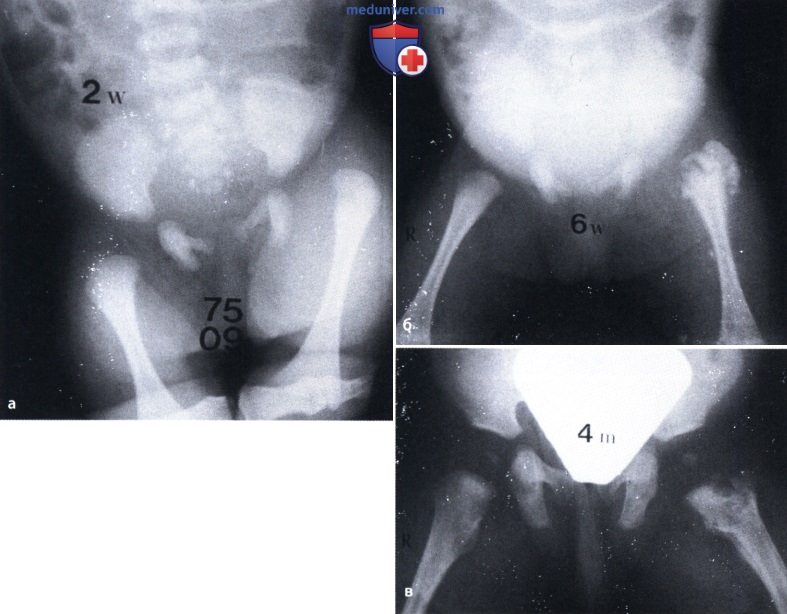

Фотографии и схемы: Коксит правого тазобедренного сустава